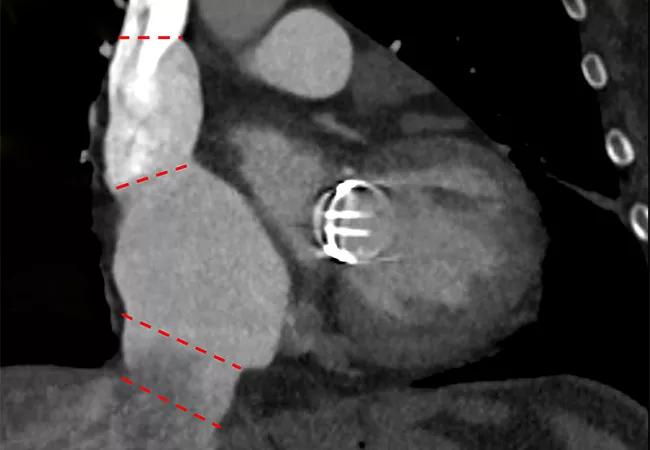

Figure. Cardiac CT measurements of venae cavae dimensions at various levels. IVC = inferior vena cava; RA = right atrium; SHV = suprahepatic veins; SVC = superior vena cava; PA = pulmonary artery.

Results included the following (see Figure):

• Inferior and superior VC dimensions — including offset between the VC axes, and the angle and height to the center of the TV annulus — were significantly larger in the severe TR cohort compared with the other groups.

• No significant differences were observed between systole and diastole within the groups in the following areas: (1) the right atrial junction levels of both the superior and inferior VC; (2) the level of the pulmonary artery for the superior VC; (3) the level of the suprahepatic vein junction of the inferior VC.